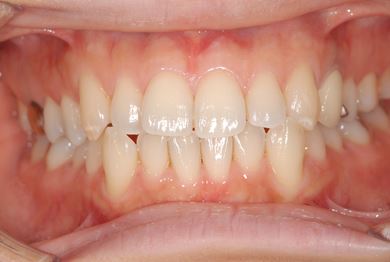

| 性別/年齢 | 女性 / 34歳 | ||||||||||||||||||||||||||||||||

| 主訴 | 以前虫歯を治療して金属を入れたところが、再び虫歯になったのか、軽くしみたり違和感がある。 | ||||||||||||||||||||||||||||||||

| 治療方針 | セラミック治療にて、審美的回復を行う。 | ||||||||||||||||||||||||||||||||

| 治療内容 | メタルボンドセラミッククラウン1本(メタルボンド用土台1本) | ||||||||||||||||||||||||||||||||

| 総治療費 | 125,685円 | ||||||||||||||||||||||||||||||||

| 治療期間 | 3ヶ月 |